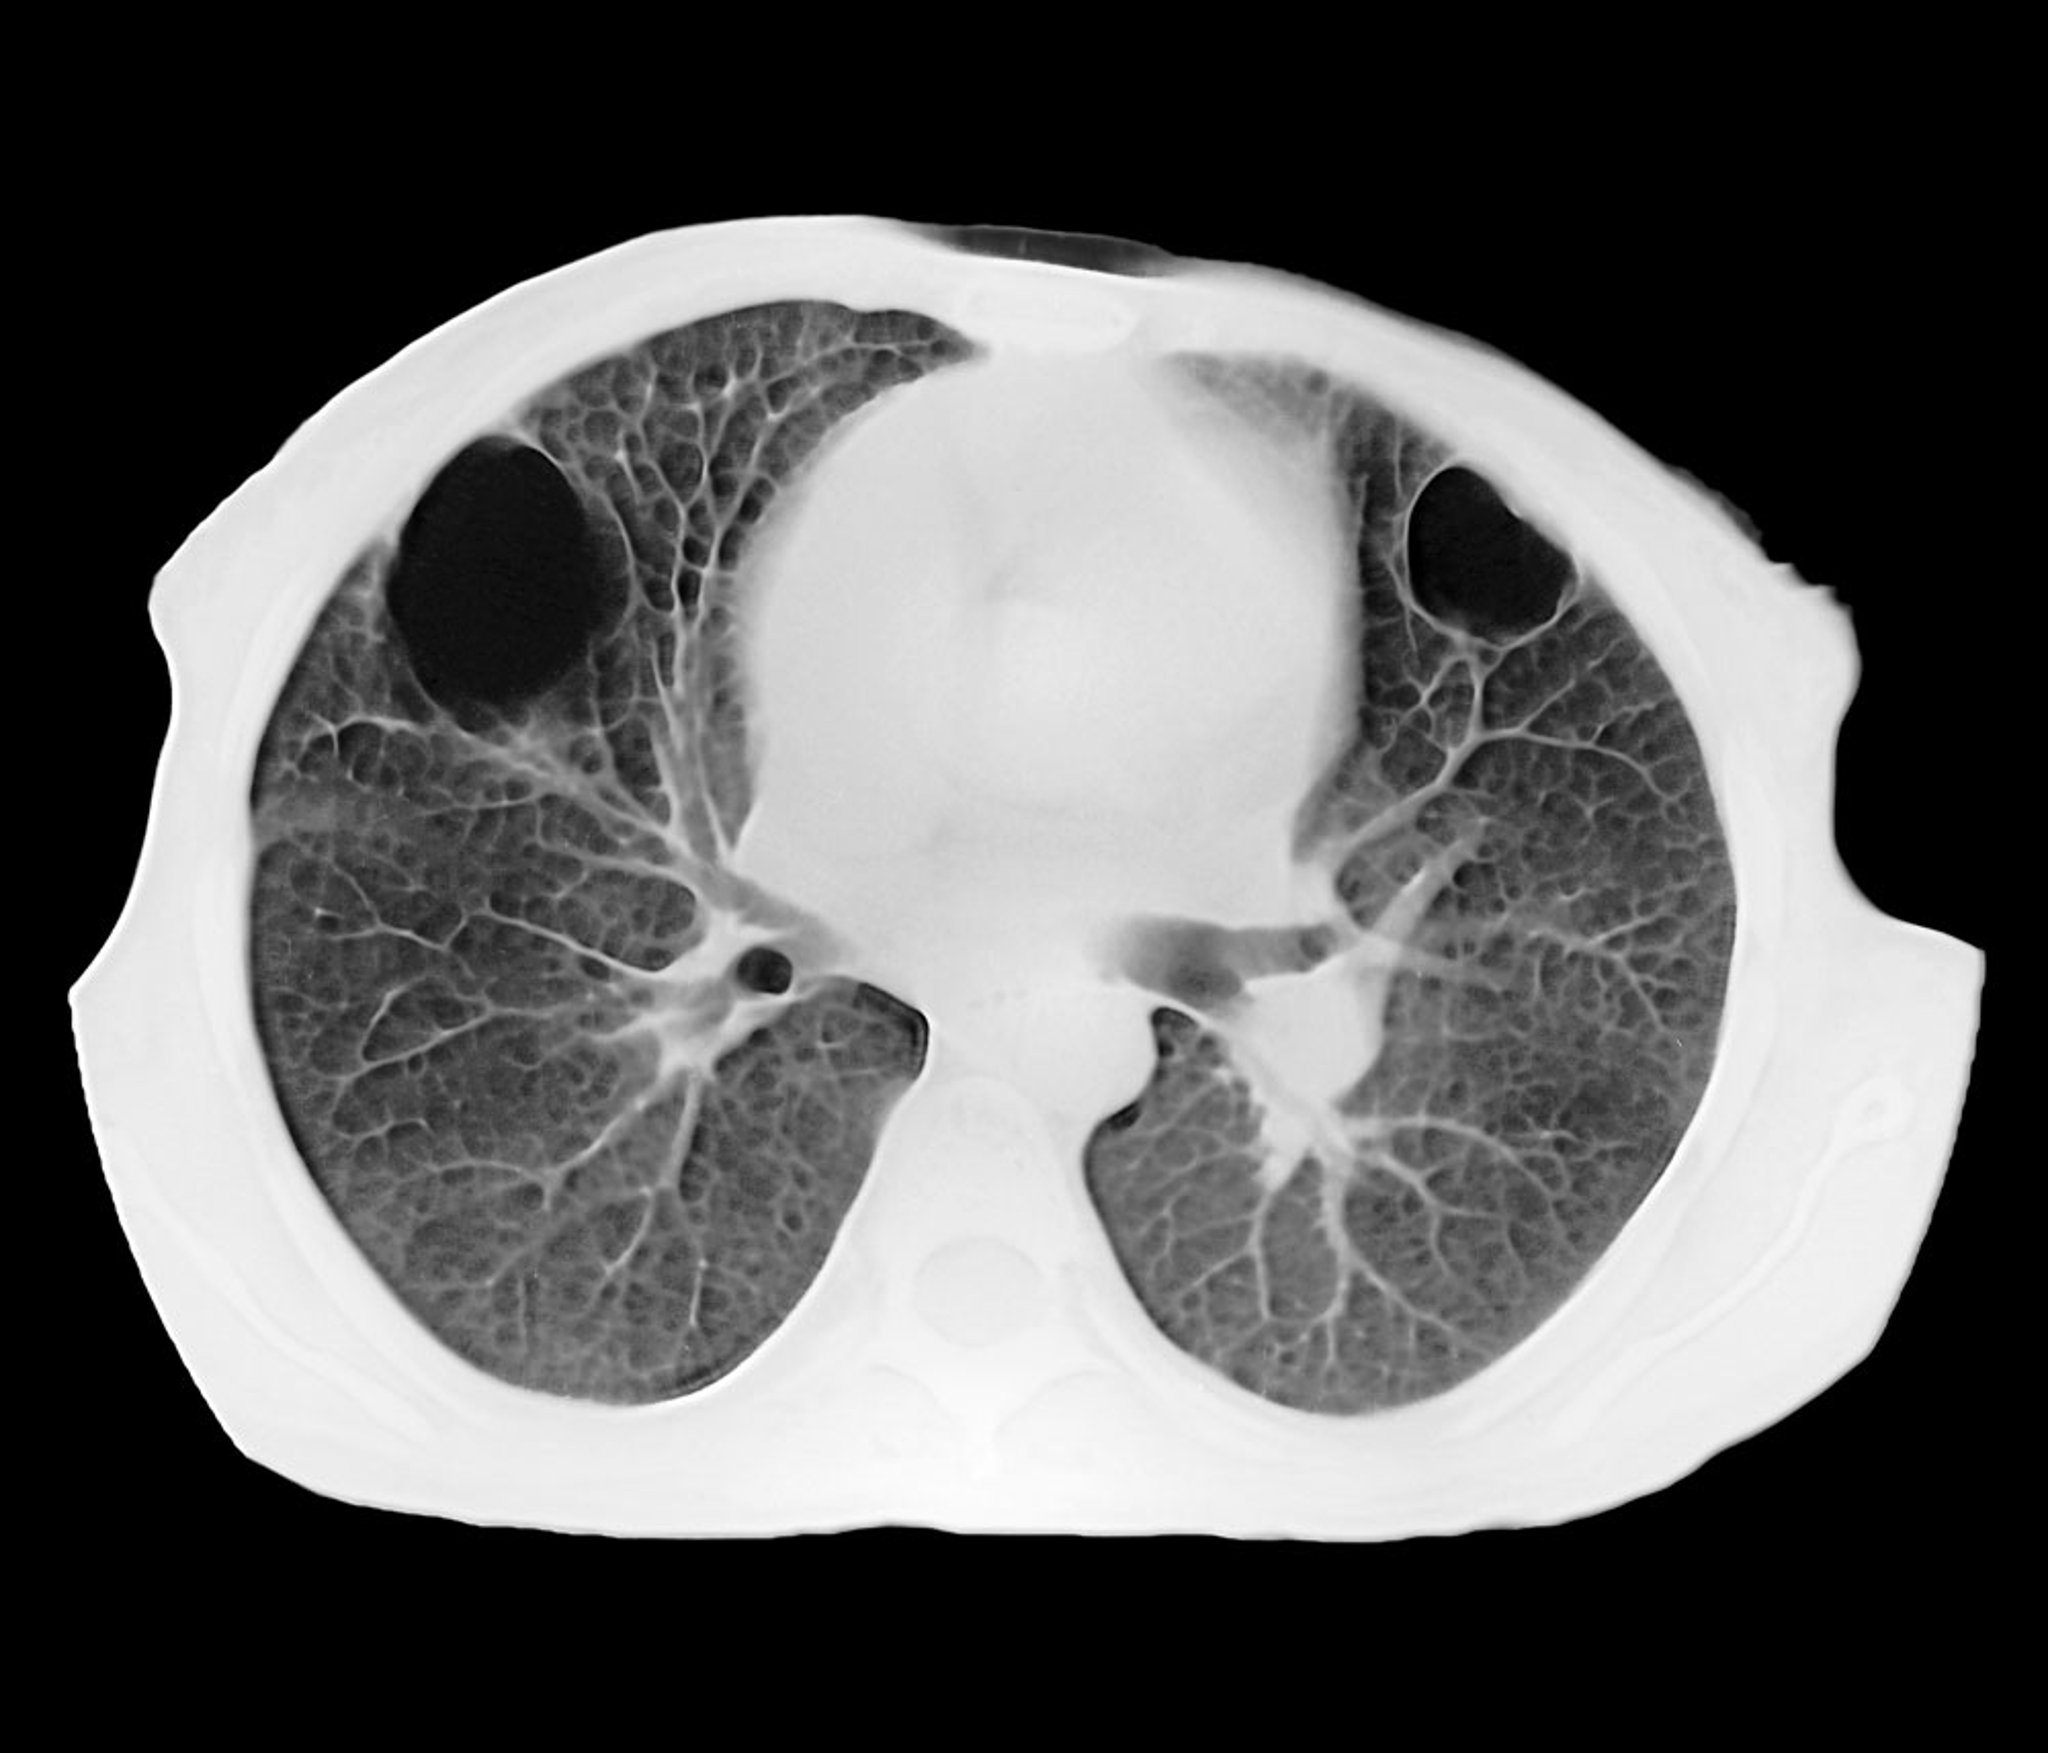

Lung Abscess (CT Scan)

This axial CT shows 2 well-circumscribed parenchymal lung abscesses in the anterior right and left lobes. The black interior corresponds to an accumulation of pus.